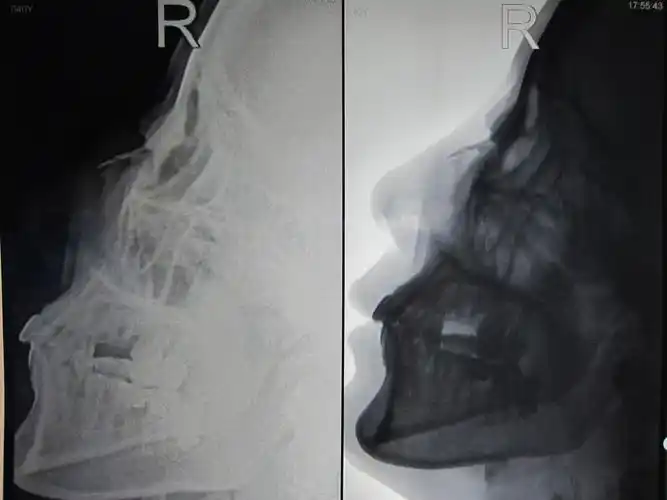

ct51740:鼻骨ct,请会诊!

第三天感觉还是不舒服就去了医院检查,去做了ct三位重建,花了230,结果

外伤致鼻骨骨折,颜面部皮肤软组织肿胀(附检查单,ct,x片).